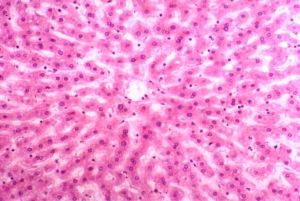

2.組織病理學檢查肉眼見結腸黏膜淺表性壞死和潰瘍形成,或黏膜全層壞死。鏡檢可見黏膜下增生的毛細血管、成纖維細胞和巨噬細胞;黏膜下動脈中可有炎症改變和纖維蛋白栓子;黏膜固有層可呈透明樣變性;肉芽組織周圍可有嗜酸性粒細胞和含血紅蛋白鐵的組織細胞浸潤。慢性期表現為病變部位與正常黏膜組織相間的黏膜腺體損傷和腺體再生。黏膜腺體數量減少或黏膜固有層內纖維組織的存在提示原有的病變比較嚴重。